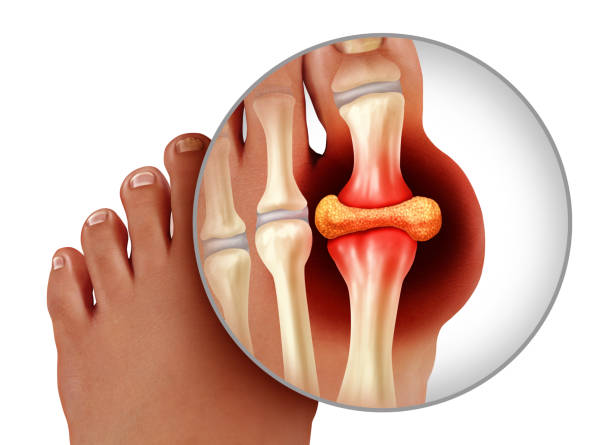

통풍은 요산이 체내에 가득하게 쌓이면서 생기는 질환입니다. 요산은 우리가 먹은 음식이 소화되고 최종적으로 남은 물질로 혈액 내 녹아 소변으로 배출되는데 요산이 과도하게 쌓이면 결정체로 변하게 되고 이 결정체가 관절 내에 침착하여 염증을 유발하게 되기 때문에 이번 시간에는 통풍 증상과 통풍 치료법에 대해 알아보도록 하겠습니다.

통풍 증상 두 번째는 엄지발가락 통증입니다. 처음에 주로 엄지발가락 근저부 관절에 발병하는데 돌발적인 통증과 함께 붉게 부어오르며 무릎, 손목, 발목, 팔꿈치 등에 발생하기도 합니다.

통풍 증상 네 번째는 급성 통풍 발작인데 엄지발가락, 발목 등 한 곳의 관절이 갑자기 빨갛게 부어오르고 손댈 수 없을 정도로 통증이 심한데 발뒤꿈치, 팔목, 손가락, 귀 등에서 나타나며 급성 통풍성 관절염이라고 부르기도 합니다.